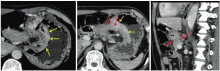

全腹CT平扫+增强影像学:胃小弯-胃窦部胃壁增厚, 最厚约16 mm, 增强扫描呈明显不均匀强化, 胃小弯侧及胃周淋巴结肿大, 最大12 mm× 11 mm, 余腹腔脏器未见明显转移病灶。影像学诊断:胃小弯至胃窦部胃壁改变, 符合胃癌, 不除外周围淋巴结转移。见图1。

王秋实(影像科主任医师):目前对于胃癌的术前分期, 最为常用的为多排螺旋CT, 以美国癌症联合会(AJCC)第7版TNM分期系统为依据[1]。其中T分期的CT诊断标准为:T1a期肿瘤局限于黏膜层内; 多排螺旋CT上肿瘤表现为内层黏膜强化和(或)黏膜增厚。T1b期肿瘤局限于黏膜下层; 多排螺旋CT上条状低密度层破坏< 50%厚度。T2期肿瘤局限于固有肌层, 多排螺旋CT上条状低密度层破坏≥ 50%厚度, 与略高密度的外层不相邻。T3期肿瘤局限于浆膜下; 多排螺旋CT上强化的肿瘤与外层已不可分, 外层外侧缘光滑或胃周脂肪界面少量线条状影。T4a期肿瘤侵犯浆膜层; 多排螺旋CT上外层外侧缘结节状或不规则和(或)胃周脂肪界面致密带状浸润。T4b期肿瘤侵犯邻近结构; 多排螺旋CT上胃肿瘤与邻近器官的脂肪界面消失或直接侵犯邻近器官。根据此项标准多排螺旋CT胃癌总的T分期准确率为77.2%~82.7%[2]。该患者的T分期表现(见图2):胃小弯和胃窦部胃壁明显增厚并异常强化(黄色箭头), 局部浆膜面外凸毛糙(白色箭头), 病变处胃周脂肪层密度增高, 见索条状致密影; 病变处胃壁与胰腺之间脂肪界面消失, 并经矢状位重建进一步证实(红色箭头)— — T4b。N分期:AJCC胃癌N分期体系建立在淋巴结转移数目的基础上, 如何在多排螺旋CT图像上判定区域性淋巴结转移成为关键。目前尚无一个被广为认可的淋巴结转移多排螺旋CT评价标准, 阳性淋巴结的判断建议采用多因素综合判断:(1)淋巴结大小(胃周淋巴结短径> 6 mm、胃周以外淋巴结短径> 8 mm); (2)形态改变(淋巴结形态饱满近乎圆形、淋巴门消失); (3)强化方式(显著强化超过80或100 HU、不均匀强化、中心坏死); (4)局部淋巴结成簇分布(数目> 3个); (5)胃癌的分型(Borrmann Ⅲ 或Ⅳ 型)。结合淋巴结大小、形态、密度及强化综合考虑, 该患者胃周共6枚淋巴结考虑转移可能性较大(见图3)— — N2。M分期:该患者未发现其余远处脏器、远处淋巴结和腹膜转移, 因此为M0。综上, 该患者的术前分期为:cT4bN2M0。